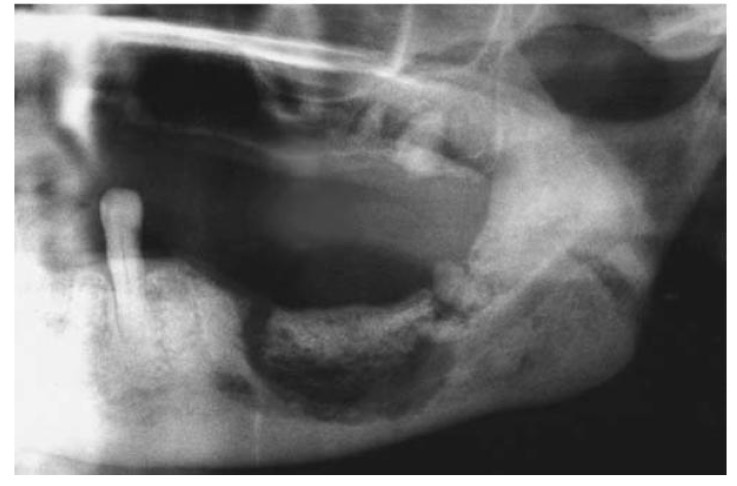

CHẨN ĐOÁN ?

HOẠI TỬ XƯƠNG HÀM SAU XẠ TRỊ